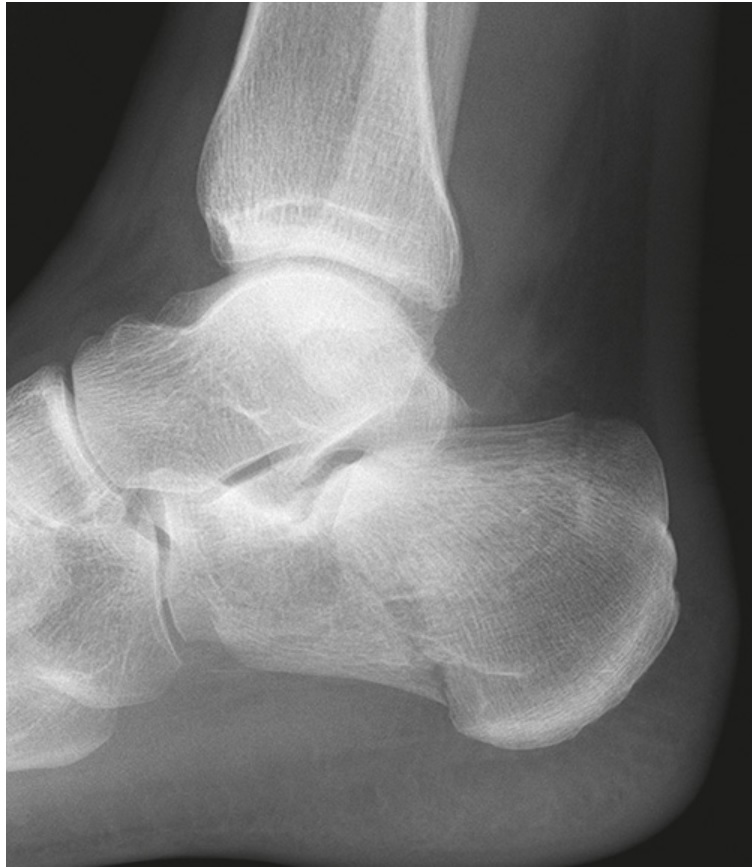

X-rays are the primary imaging tool used to diagnose boxer’s fractures. Typically, images are taken from three different angles to provide a comprehensive view of the hand’s bone structure. In some cases, additional specialized views may be necessary to detect hard-to-find fractures.

X-rays can also reveal the presence of foreign bodies in the hand, such as glass, metal, or stone fragments, which may have been introduced during the injury.

Continued

Typically, the X-rays look at the hand from three different directions. Getting images from different angles makes it easier for the doctor to see possible fractures. They should be able to see if there’s a break and if so, tell what type it is. Sometimes, the doctor may order more X-rays, with special views to look for hard-to-find fractures.

Imaging tests are ordered, as well, even if the doctor is sure of their diagnosis. This is typically an X-ray image, which can confirm or determine, which bone is broken. Confirming the diagnosis through X-ray is critical, as treatment can vary greatly, again, depending on, which bones in the hand are damaged.

- X-ray: AP and Oblique view should be obtained; lateral views can help with assessing angulation and other injuries in the carpometacarpal area.

Physical examination of a boxer’s fracture focuses on determining the orientation of the fracture and its effect on the rotation of the small finger. The examination needs to make sure that there is no overlap of the small finger on the ring finger or significant divergence from the ring finger when compared to the other side. A complete neurovascular examination of the hand and small finger is performed to make sure that the nerves and vessels to the finger are uninjured. Radiographs, or x-rays, of the hand in multiple planes are used to determine the fracture orientation, including angulation and displacement.